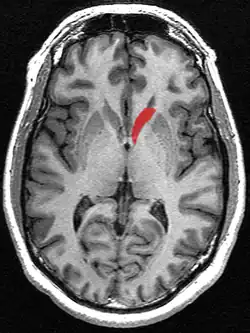

Transverse cut of brain (horizontal section), basal ganglia is blue | |